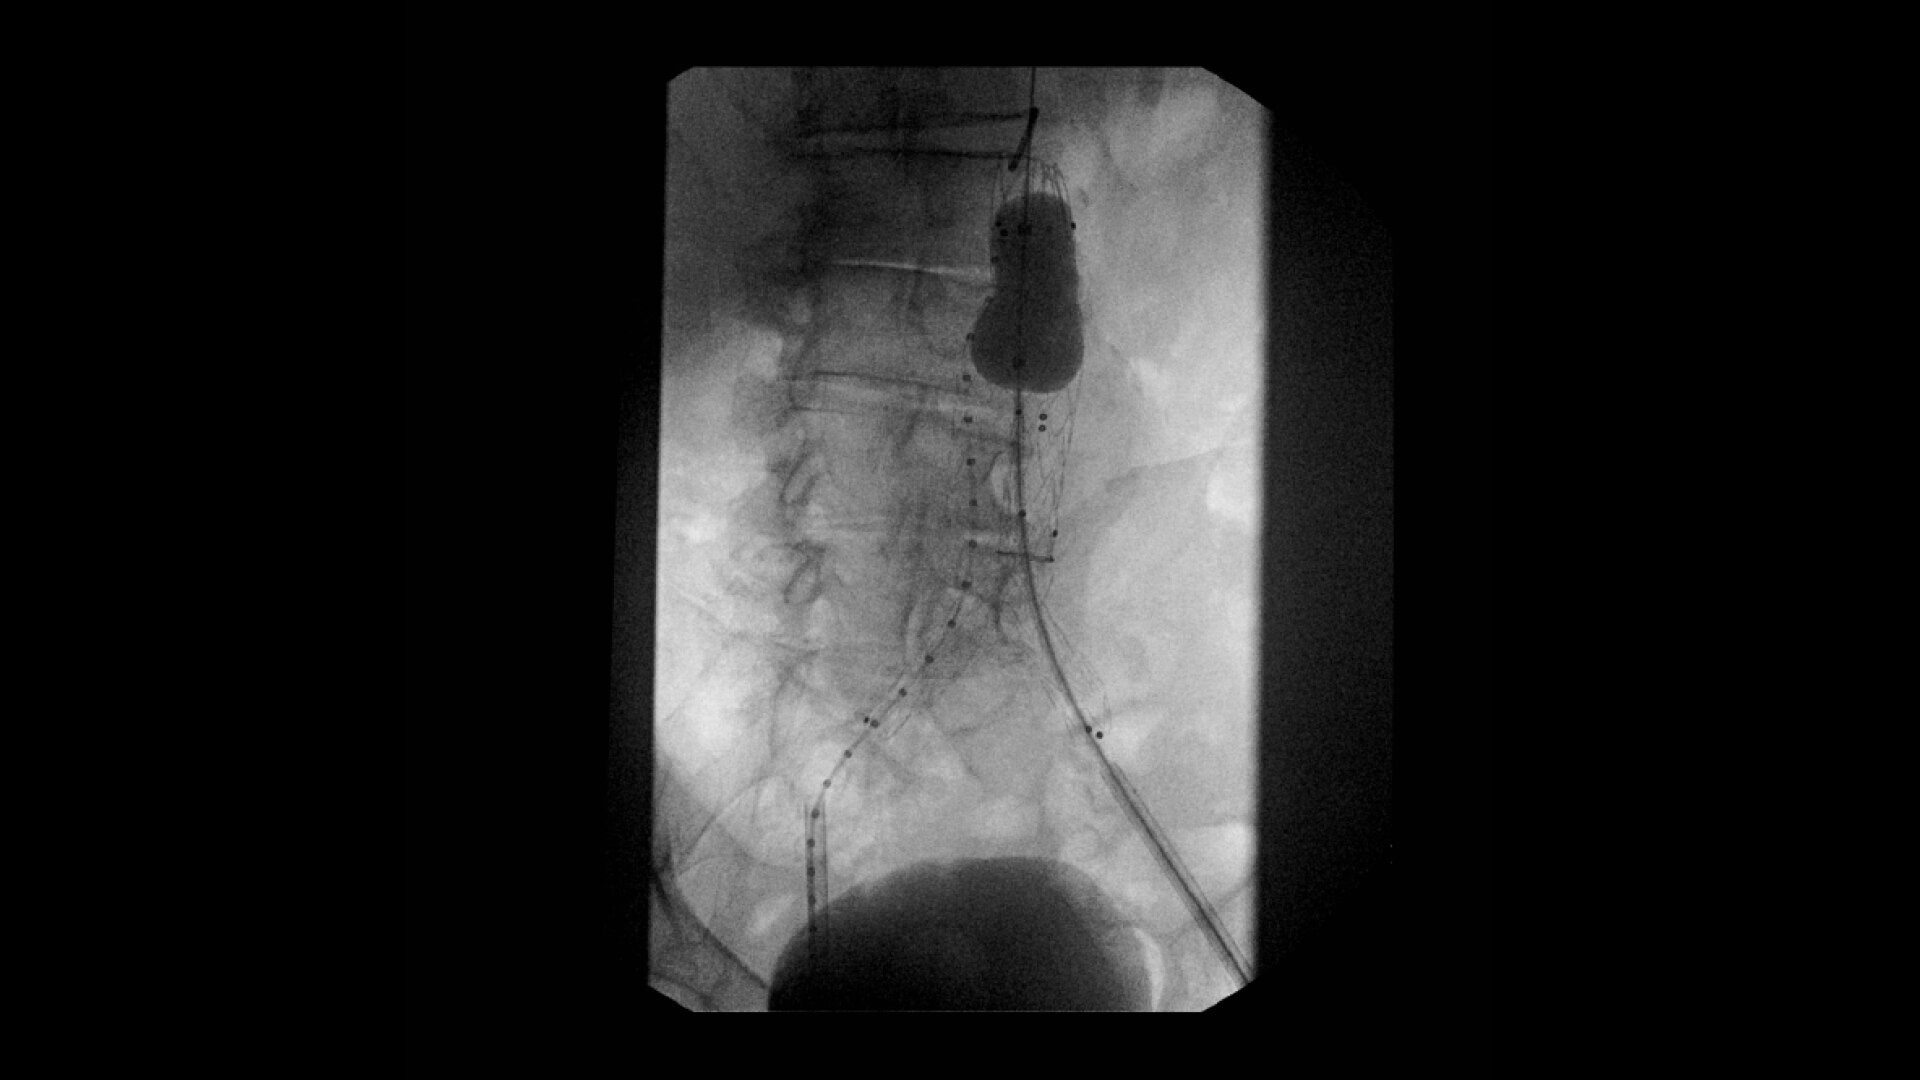

OEC C-arms are used by interventionalists and surgeons to obtain vascular imaging during peripheral to contrast run-off procedures. Superb resolution, even in the presence of motion, enables easy identification of anatomical landmarks and the extremity of the catheter, even as catheter tip moves.

Clearly see 0.014” guidewires in chest and abdomen region or 0.008” guidewires in peripheral vascular with the OEC Elite CFD with a flat detector, image processing advancements and 4K viewing display.

Experience fixed room-like images with eNR (enhanced Noise Reduction), an advanced software algorithm that automatically reduces image noise by 30% for an equivalent appearance of 30 kW power.

Perform a full leg Bolus Chase in one contrast run with a Preset Profile that includes Motion Tolerant Subtraction, that dynamically adjusts image quality based on presence of motion.

During contrast run-off procedures, easily select contrast type with positive (e.g. Iodine) or negative (e.g. Carbon Dioxide) during subtraction. The OEC Elite CFD cardiovascular package also includes Roadmapping.

Complex vascular procedures require powerful imaging systems. OEC premium C-arms perform in a variety of procedures such as:

•Abdominal aortic aneurysm (AAA) stent and balloon deployment

• Infrarenal aortic aneurysm repair

• Recanalization and stent placement in iliac arteries